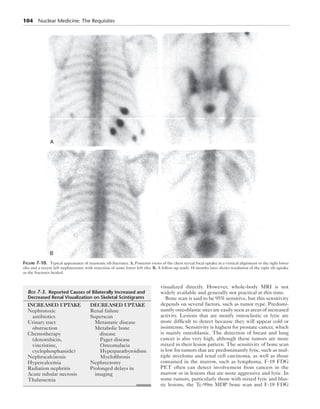

Figure 7-10. Typical appearance of traumatic rib fractures. A, Posterior views of the chest reveal focal uptake in a vertical alignment in the right lower

ribs and a recent left nephrectomy with resection of some lower left ribs. B, A follow-up study 18 months later shows resolution of the right rib uptake

as the fractures healed.